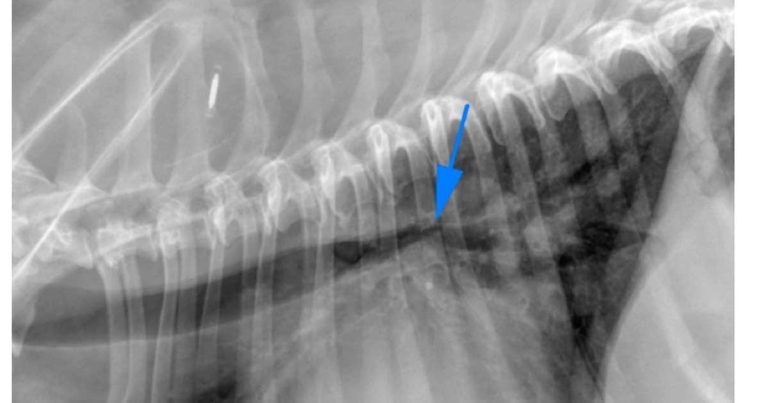

Some patients may have primary cardiovascular disease, which can mimic lower respiratory tract disease – for example, left mainstem bronchus compression due to significant left atrial cardiomegaly in patients with advanced mitral valve disease (Figure 1). Other patients may even have a combination of primary cardiovascular disease and chronic lower respiratory tract disease – for example, geriatric terrier breeds with mitral valve disease and concurrent bronchomalacia1.